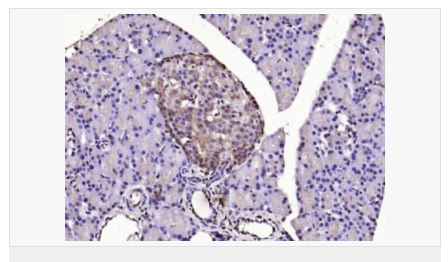

交叉反應(yīng):Human,Mouse,Rat(predicted:Dog,Pig,Cow) 推薦應(yīng)用:WB,IHC-P,IHC-F,ICC,IF,ELISA

產(chǎn)品應(yīng)用WB=1:500-2000 ELISA=1:5000-10000 IHC-P=1:100-500 IHC-F=1:100-500 ICC=1:100-500 IF=1:100-500 (石蠟切片需做抗原修復)